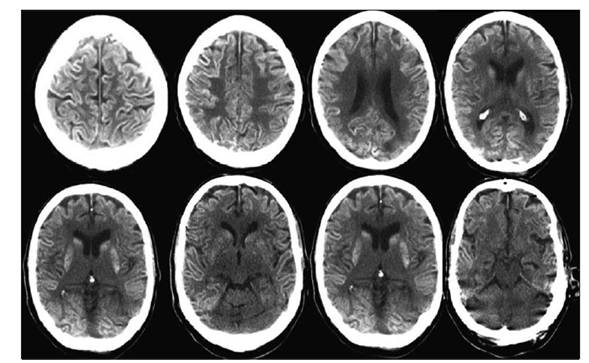

Presentamos el caso de un paciente de sexo masculino de 64 años con antecedentes de diabetes e hipertensión arterial. En enero del año 2007 se realizó diagnóstico anátomo-patológico de carcinoma superficial de células transicionales de vejiga, realizándose resección transuretral (RTU). En el seguimiento posterior, en julio del 2010, se diagnosticó recidiva de lesión vesical que se resecó por RTU y la anatomía patológica informó carcinoma de células transicionales, papilar (grado 2 de la Organización Mundial de la Salud), sin invasión submucosa. Luego de la RTU recibió tratamiento con BCG intravesical semanalmente durante seis semanas con buena evolución. Presentó nueva recidiva tumoral en julio de 2013 tratada con nueva RTU. Se inició nueva serie de tratamiento con instilaciones intravesicales de ampollas de 80 mg de BCG, inicialmente una instilación semanal durante seis semanas y posteriormente una instilación mensual por seis meses. Presentó buena respuesta y se indicó continuar con una instilación mensual desde julio a diciembre de 2014. Subsiguientemente a las dosis de setiembre, octubre y noviembre presentó fiebre, dolor hipogástrico, disuria y malestar general que persistieron por 24 a 72 horas. En las 24 horas siguientes a la sexta instilación (realizada el 15 de diciembre de 2014) presentó fiebre, disuria, tos y expectoración mucosa, síntomas que motivaron el ingreso hospitalario a las 24 horas de la instilación. Al examen clínico se auscultaron estertores crepitantes a nivel pulmonar y con el planteo clínico de infección respiratoria se inició tratamiento con ceftriaxona. El hemograma mostró leucocitosis periférica de 12.800 celulas/µl con neutrofilia (95%) y presentó elevación de biomarcadores inflamatorios (proteína C reactiva de 192 mg/l, velocidad de eritrosedimentación de 45 mm/h). El examen de orina presentó una densidad de 1025, pH 5,0, proteínas 0,80 mg/dL, en el sedimento abundantes leucocitos (campos cubiertos), cilindros granulosos 3/campo, prueba de esterasa leucocitaria positiva, test de nitritos negativos, el urocultivo no presentó desarrollo y la búsqueda de antígeno neumocócico en orina mediante la prueba BinaxNow® fue negativa. A las 24 horas de la internación instaló un síndrome de disfunción orgánica múltiple (DOM) con compromiso de conciencia, injuria renal aguda (creatininemia de 5 mg/dl, azoemia 1,26 g/l y oligoanuria), insuficiencia respiratoria asociada a síndrome de distrés respiratorio agudo (SDRA), disfunción hepática (bilirrubina total 4,01 mg/dl, bilirrubina directa 3,04 mg/dl, fosfatasa alcalina 602 U/l, transaminasa glutámico oxalacética 231 U/l, transaminasa glutámico pirúvica 210 U/l, gama glutamiltranspeptidasa 384 U/l, láctico deshidrogenasa 1693 U/l), hipoalbuminemia 2,3 g/dl y alteraciones en el estudio de la crasis sanguínea (trombocitopenia de 75.000/mm3, fibrinógeno 243 mg/dl, alteración de la tasa de protrombina con valor de 45% y KPTT 20 segundos). Ingresó a la unidad de cuidados intensivos, requiriendo sedación y analgesia, intubación traqueal, asistencia ventilatoria mecánica y tratamiento de reemplazo de la función renal mediante hemodiálisis. El nivel de hemoglobina (Hb) se redujo de 14,5 a 9,6 g/dl en los primeros días. La leucocitosis inicial fue de 18.000 leucocitos µ/l a predominio neutrófilos. Por la severidad de los síntomas neurológicos y la presencia de rigidez de nuca se realizó una punción lumbar, obteniéndose un líquido cefalorraquídeo (LCR) con presión de apertura elevada (50 cm de H20), con reacción de Pandy positiva, 0,94 g/L de proteínas, glóbulos blancos de 2 células/mm3 y glucosa de 1,09 g/L. No presentó desarrollo bacteriológico (medios para bacterias inespecíficas ni medios para micobacterias en el laboratorio de la Comisión Honoraria de la Lucha Antituberculosa) en los cultivos de LCR, hemocultivos ni cultivos de orina. La reacción en cadena de la polimerasa para micobacterias en secreciones traqueales y LCR fue negativo, tampoco se observó amplificación del genoma correspondiente a herpes virus tipo I, II, varicela-zóster, Epstein Barr, citomegalovirus ni adenovirus en LCR. La tomografía computarizada (TC) de cráneo evidenció aumento de la diferencia de la densidad entre la sustancia gris y blanca predominantemente en región supratentorial, con reintensificación espontánea y con contraste intravenoso de las zonas corticales cerebrales, mostró además aumento de la hipodensidadperiventricular sugestivo de edema transependimario(Figura 1).

Figura 1 Tomografía computarizada de cráneo al ingreso a la unidad de cuidades intensivos. Se evidencia aumento de la diferencia de la densidad entre la sustancia gris y blanca predominantemente en región supratentorial con reintensificación espontánea y con contraste intravenoso de las zonas corticales cerebrales; aumento de la hipodensidad periventricular sugestivo de edema transe pendimario

El electroencefalograma (EEG) demostró características sugestivas de disfunción cerebral difusa severa, sin actividad paroxística. Por la situación clínica del paciente no fue posible el traslado para la realización de resonancia magnética. La situación neurológica y la elevada presión de apertura del LCR pudieron ser manifestaciones de hipertensión intracraneana, la que se trató mediante medidas generales tales como sedación y analgesia, alineación cefálica, cabecera elevada a 30°, se aseguró una presión arterial media mayor a 90 mm Hg para mantener una presión de perfusión cerebral estimada próxima a 70 mm de Hg, se mantuvo una PaCO2 próxima a 35 mm de Hg, se optimizó la oxigenación tisular manteniendo PaO2 y niveles de Hb en sangre adecuados y se realizó osmoterapia con suero salino hipertónico. Cabe destacar que no se realizó monitorización invasiva de presión intracraneana, asimismo con la salvedad de que la TC no es una herramienta utilizada para medir presiones, las imágenes tomográficas iniciales no evidenciaron lesiones que determinaran efecto de masas sugestivas de hipertensión intracraneana ni aparecieron en la evolución lesiones estructurales secundarias a hipertensión intracraneana persistente. El edema transependimario observado se produce por cualquier alteración patológica, grave, que afecte el circuito de producción-reabsorción del LCR; este tipo de edema cerebral es secundario, en la mayoría de los casos, a un aumento de la presión intraventricular, es transitorio y desaparece espontáneamente cuando se corrige la hipertensión intraventricular. En una segunda punción lumbar realizada a las 72 horas de tratamiento (extracción de muestras para estudio de virus por biología molecular) la presión de apertura fue normal.

El paciente presentó mejoría de las disfunciones respiratoria, renal, hepática y de la crasis, pero persistió con afectación neurológica. El coma persistió durante aproximadamente 15 días, posteriormente presentó un despertar tardío que se caracterizó por recuperación de los ciclos de sueño-vigilia, sin contenido de conciencia y con una cuadriparesia flácida sin reflejos osteo-tendinosos. El EEG luego de más de diez días de suspendida la sedoanalgesia informó elementos de sufrimiento cerebral difuso severo y las TC posteriores no mostraron cambios significativos salvo resolución del edema transependimario. Se realizó traqueostomía y se desvinculó de la ventilación mecánica, manteniendo una situación respiratoria y hemodinámica estable, recuperando la funcionalidad renal pero sin recuperar funciones encefálicas superiores, manteniendo un despertar espontáneo y a los estímulos nociceptivos, pero sin respuesta facial ni espinal y sin responder ante otros estímulos ni interactuar con el ambiente. Falleció a los 70 días de evolución en la unidad bajo directivas de adecuación del esfuerzo terapéutico, priorizando los cuidados del con fort, luego de información y resolución en conjunto con la familia.